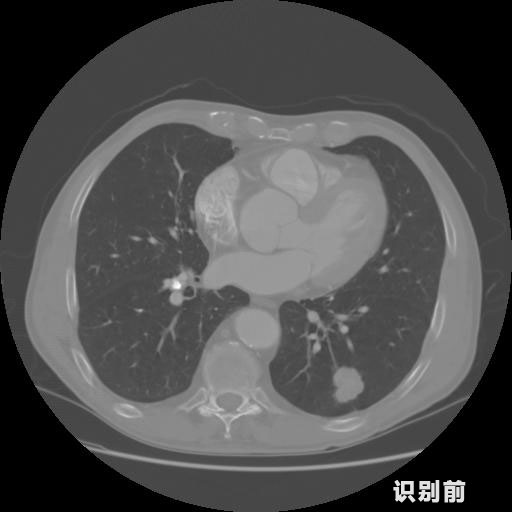

英特健康AI深度學習醫(yī)療圖像識別系統(tǒng)案例_胸部CT

報告:

1.發(fā)現(xiàn)肺結節(jié)的可能性為95.56%---位于框指數(shù)位置:[331.70554 366.13406 365.21707 403.96234]